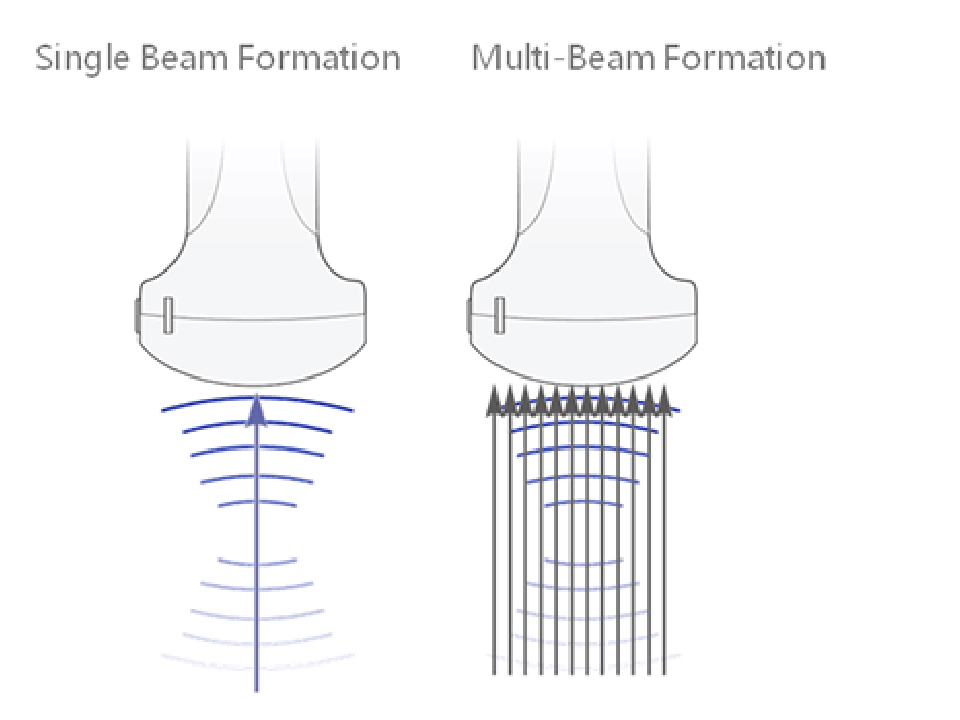

iBeamTM

Permits use of multiple scanned angles to form a single image, resulting in enhanced contrast resolution and improved visualization.